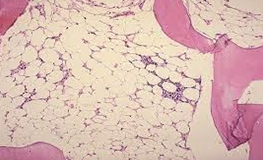

Further investigations revealed, bone marrow aspirate and biopsy showed hypocellular marrow (10%- 20%) with reduced trilineage hematopoiesis. Normal Chromosomal breakage study was done to rule out any genetic etiology. Paroxysmal Nocturnal Hemoglobinuria(PNH) clone was found on 59% of neutrophils and monocytes by flow cytometry. With all the workup, she was diagnosed with severe Aplastic Anemia.